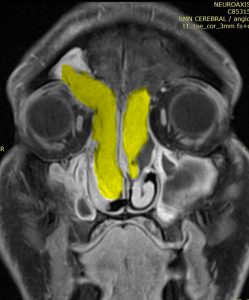

Examenul IRM cerebral cu substanță de contrast (dr. Emilia Diaconu) evidențiază o formațiune tumorală hipervascularizată cu origine în sinusul frontal stâng, cu extensie în sinusul frontal drept, etmoid bilateral și în ambele fose nazale. Are raporturil cu tavanul orbitei drepte/mușchiul oblic superior drept, lama papiracee, canalul arterei etmoidale anterioare drepte tavanul etmoidal/foveea etmoidală, lama cribriformă/fosele olfactive/bulbi olfactivi, perforează septul nazal anterosuperior, distruge cornetele nazale mijlocii, deviază infero-lateral și comprima cornetul inferior drept, cu obstrucția porului extern al canalului lacrimonazal și dilatația sacului lacrimal drept. Are aferențe arteriale din artera angulară, artera infraorbitală și artera sfenopalatina, mai evidente/cu calibru mai mare de partea dreaptă. Fina încărcare cu contrast a durei mater frontal, liniar, uniform, net conturat, mai extins de partea dreaptă, fără anomalie de semnal în parenchimul adiacent – sugerează, mai degrabă, aspect inflamator/reactiv (fig. 1,2)

Fig. 1,2: aspect RMN cu sc. – origine tumorala in sinusul frontal drept, invazie rino-etmoidala bilaterala